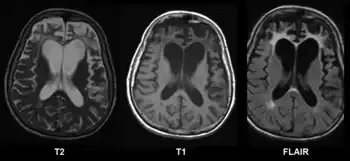

| Brain MRI of a 65-year-old woman with frontotemporal dementia. Cortical and white matter atrophy of the frontal lobes is clear in all images. | |